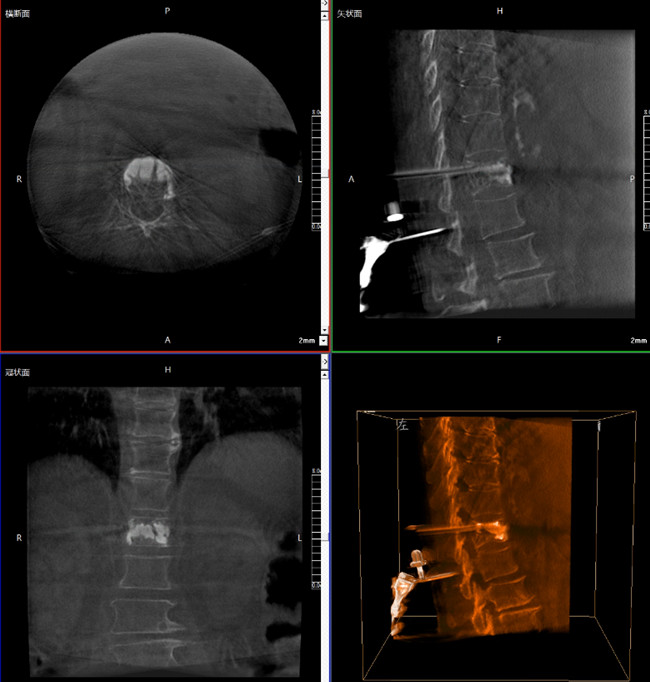

使用普愛(ài)醫(yī)療三維C形臂對(duì)患者進(jìn)行胸椎影像掃描及三維重建,圖像被同步傳輸?shù)狡諓?ài)醫(yī)療骨科機(jī)器人導(dǎo)航系統(tǒng)。

借助骨科機(jī)器人的規(guī)劃軟件進(jìn)行術(shù)前手術(shù)路徑模擬規(guī)劃,找到穿刺位置和角度,操作機(jī)械臂快速完成手術(shù)入點(diǎn)的準(zhǔn)確定位。

*術(shù)前規(guī)劃